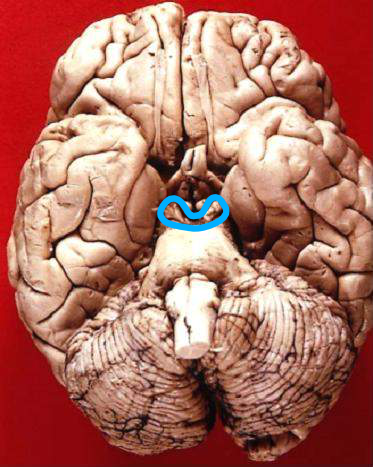

আসলে আমাদের মস্তিষ্কের “সেরিব্রাল কর্টেক্স” ও “থ্যালামাস” অংশদুটির সংযোগকারী যে নিউরাল লুপগুলিতে গামা তরঙ্গ বয়ে চলে সেগুলি আমাদের মস্তিষ্কে সংগৃহীত দৃষ্টি, শব্দ, ও ভাষা সম্বন্ধীয় তথ্যগুলি থেকে স্থানিক উপাংশকে নিষ্কাশন করে; এবং গামা তরঙ্গ বহনকারী যে নিউরাল লুপগুলি “সেরিব্রাল কর্টেক্স”-র সাথে “মিডব্রেইন” অংশকে সংযুক্ত করে সেগুলি সংগৃহীত তথ্যগুলি থেকে সময়গত উপাংশকে বেছে দেয়।

মিডব্রেইন